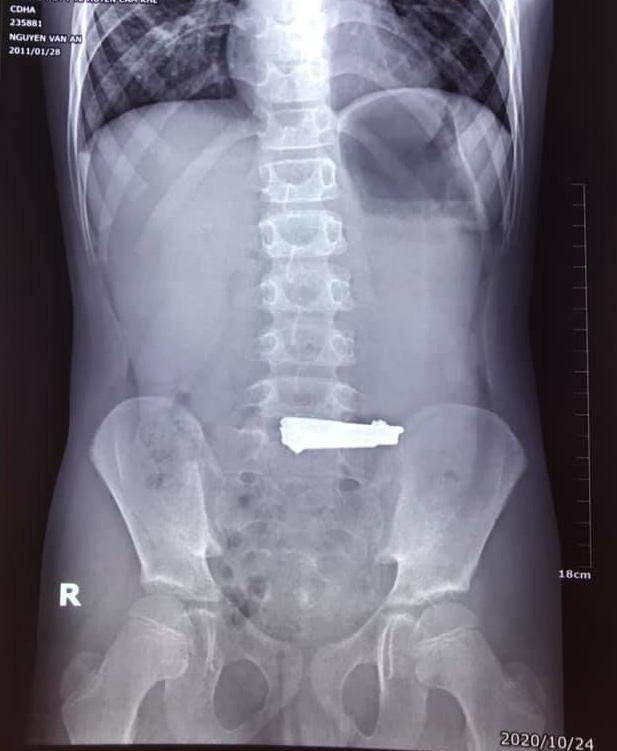

Vị trí của chiếc bấm móng tay trong cơ thể cháu bé 9 tuổi

Như VTV đưa tin, sau khi tiến hành nội soi dạ dày, các bác sĩ phát hiện một chiếc bấm móng tay có kích thước 60x16mm nằm tại vị trí phình vị lẫn vào thức ăn khiến niêm mạc dạ dày bị tổn thương.